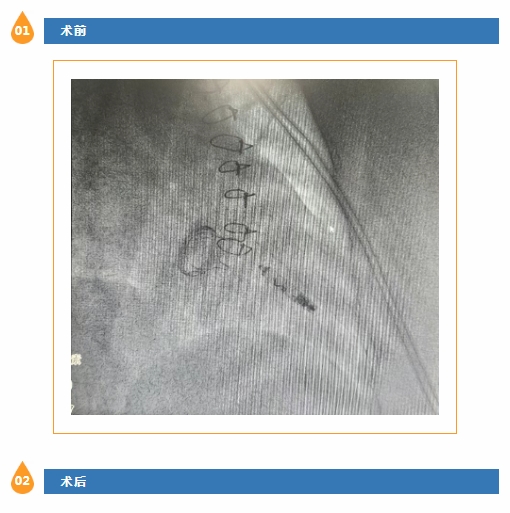

手术过程中,在数字减影血管造影的引导下,昃峰教授和蔡主任团队密切配合,通过精准操作,将仅2克重的Aveir起搏器顺利送达右心室理想位置,并设置理想参数。手术顺利完成。在起搏器的保护下,抗心律失常药物的使用使者的快速房颤得到有效控制。术后患者恢复令人欣喜。陈阿姨不仅很快可以下床活动,“再也不用提心吊胆地生活了!”患者质朴的话语道出了最真实的感受。